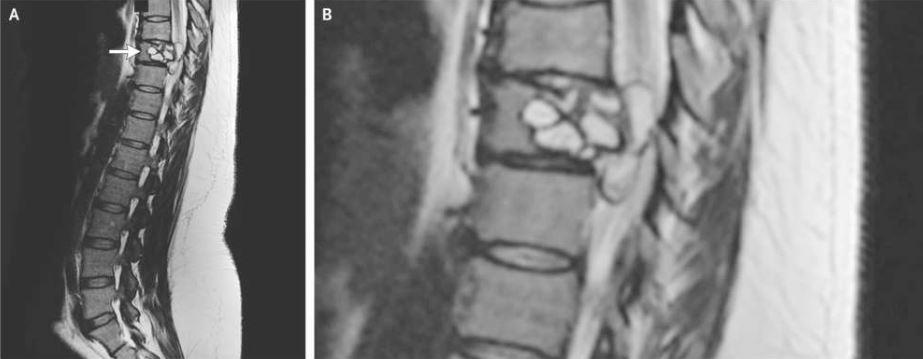

Μια μαγνητική τομογραφία αποκάλυψε μια βλάβη στη σπονδυλική της στήλη, στον ένατο θωρακικό σπόνδυλο, ο οποίος βρίσκεται στην μέση της πλάτης.

Η γυναίκα χρειάστηκε χειρουργική επέμβαση για την αφαίρεση της βλάβης και οι εξετάσεις αποκάλυψαν ότι προκλήθηκε από μόλυνση με Echinococcus granulosus, μια μικρή ταινία που βρίσκεται σε σκύλους και ορισμένα ζώα φάρμας, όπως πρόβατα, βοοειδή, κατσίκες και χοίρους.